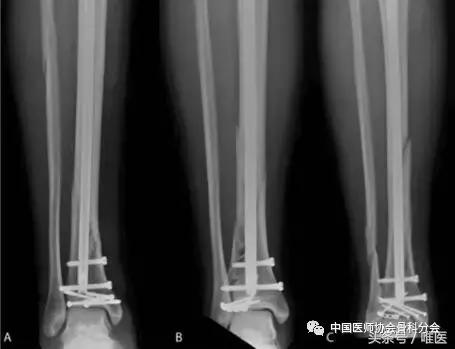

点状复位钳可放置在皮肤小切口,复位关节面的骨折线,然后使用导向技术放置螺钉,可以使用实心或空心螺钉,螺钉尽可能垂直于骨折线并靠近关节面。当需要对胫骨远端切开复位时,依据下肢软组织损伤情况决定手术时机。应尽可能使用有限切口或多个小切口复位和固定关节,接骨板和螺杆可用于支撑粉碎区域或关节撞击区域。如果钢板的任何部分与胫骨髓内钉深度重叠,则应透视胫骨远端和放置多枚互锁螺钉(图4)。

图4:患者A-C的最终正位射线照片显示关节内远端胫骨骨折的髓内钉固定。关节固定可以单独用经皮螺钉(A),接骨板和螺钉(B),或接骨板和螺钉(C)的组合来进行。